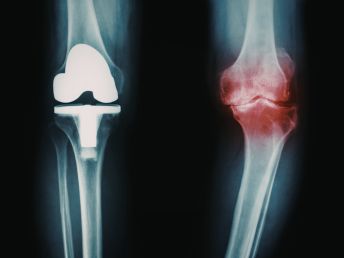

Dr S R Panda is a reputed orthopaedic surgeon in Kolkata offering advanced facilities including General & Joint Replacement OT, Arthroscopy & Trauma OT, and Spine Surgery & Sports Injury OT, ensuring precise diagnosis, modern surgical techniques, and comprehensive bone and joint care under one roof.

Advanced Orthopaedic & Joint Replacement Expertise

Advanced expertise in orthopaedic care and joint replacement surgeries ensuring precise treatment and long-lasting results.